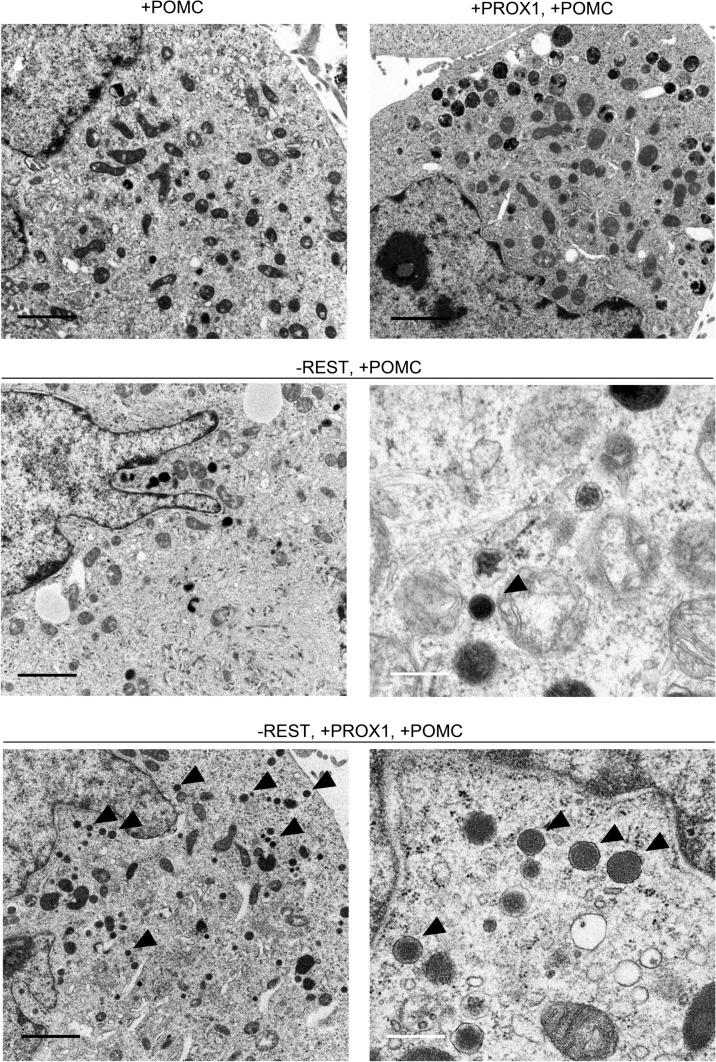

Endocrine secretory granules (ESGs) are morphological characteristics of endocrine/neuroendocrine cells and store peptide hormones/neurotransmitters. ESGs contain prohormones and ESG-related molecules, mainly chromogranin/secretogranin family proteins. However, the precise mechanism of ESG formation has not been elucidated. In this study, we experimentally induced ESGs in the non-neuroendocrine lung cancer cell line H1299. Since repressive element 1 silencing transcription factor (REST) and prospero homeobox 1 (PROX1) are closely associated with the expression of ESG-related molecules, we edited the REST gene and/or transfected PROX1 and then performed molecular biology, immunocytochemistry, and electron and immunoelectron microscopy assays to determine whether ESG-related molecules and ESGs were induced in H1299 cells. Although chromogranin/secretogranin family proteins were induced in H1299 cells by knockout of REST and the induction was accelerated by the PROX1 transgene, the ESGs could not be defined by electron microscopy. However, a small number of ESGs were detected in the H1299 cells lacking REST and expressing pro-opiomelanocortin (POMC) by electron microscopy. Furthermore, many ESGs were produced in the REST-lacking and PROX1- and POMC-expressing H1299 cells. These findings suggest that a lack of REST and the expression of genes related to ESG content are indispensable for ESG production and that PROX1 accelerates ESG production.Trial registration: Not applicable.

内分泌分泌颗粒(ESG)是内分泌/神经内分泌细胞的形态特征,并且储存肽激素/神经递质。ESG 包含前激素和 ESG 相关分子,主要是嗜铬粒蛋白/分泌粒蛋白家族蛋白。然而,ESG 形成的确切机制尚未阐明。在这项研究中,我们在非神经内分泌肺癌细胞系 H1299 中实验性地诱导 ESG。由于抑制元件 1 沉默转录因子(REST)和 prospero 同源盒 1(PROX1)与 ESG 相关分子的表达密切相关,因此我们编辑了 REST 基因,或转染了 PROX1,然后进行了分子生物学、免疫细胞化学、电子和免疫电子显微镜检测,以确定 H1299 细胞中是否诱导了 ESG 相关分子和 ESG。尽管通过敲除 REST 诱导了 H1299 细胞中嗜铬粒蛋白/分泌粒蛋白家族蛋白的表达,并且 PROX1 转基因加速了诱导作用,但电子显微镜无法定义 ESG。然而,在缺乏 REST 并通过电子显微镜表达 pro-opiomelanocortin(POMC)的 H1299 细胞中检测到少量 ESG。此外,在缺乏 REST 并表达 PROX1 和 POMC 的 H1299 细胞中产生了许多 ESG。这些发现表明,缺乏 REST 和 ESG 内容相关基因的表达是 ESG 产生所必需的,并且 PROX1 加速了 ESG 的产生。试验注册:不适用。